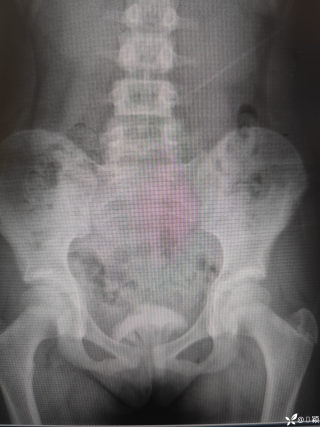

玩耍被撞后10岁男孩被诊断有肿瘤,多器官切除 当地卫健局:医院存在问题,已立案

丁香医小白普外科医师

2023年10月26日,来自山东菏泽市成武县的小烨和他家人的命运被彻底改变了。这个原本阳光、可爱的小男孩在一次意外被撞击后,在医院检查出了腹腔内存在肿瘤,并在手术中被切除了包括十二指肠、胰腺、大部分胃和小肠等多个器官。此后便无法再像正常人一样吃饭、喝水,活着要靠长期静脉注射营养液。一份2024年12月由第三方机构出具的司法鉴定意见书显示,当时给小烨做手术的成武县人民医院在该医疗行为中存在过错,与小烨的损害后果之间存在因果关系,建议医疗过错在损害后果中的原因力大小为同等原因。此外,另一份由成武县卫生健康局在2025年9月28日发出的书面答复中显示,成武县人民医院存在24小时内未完成病历;手术知情